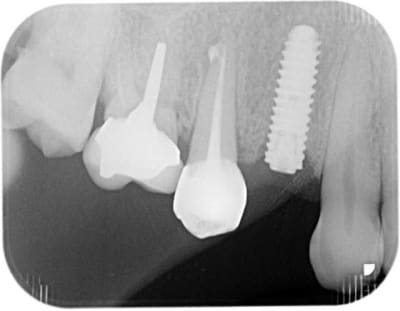

pose d'un axiom en 4*12 en juillet en sous crestal comme il le faut.

et aujourd'hui raido début de cratérisation : petite mais existante;

pour la forme et le fond pano avant retro à la pose et rétro aujourd'hui

prévu implant en 36 et l'endo de 15 avait été reprise avant pour être refaite simultanément je connais les critiques nonoliennes.